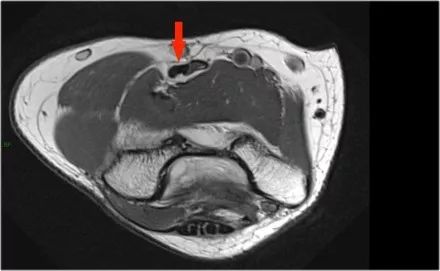

● 在MR上,异常非常明显。内侧上髁和相邻骨中存在骨髓水肿(黄色箭头)。● Little Leaguer的肘部也被称为内侧性上睑下垂,有些人称之为骨骺溶解。● 顺便说一下,如果是急性创伤事件,这也可以称为Salter-Harris I型骨折。● 注意正常的尺侧副韧带(红色箭头)。在儿童中,外翻应力的薄弱环节不是尺侧副韧带,而是骨骺。